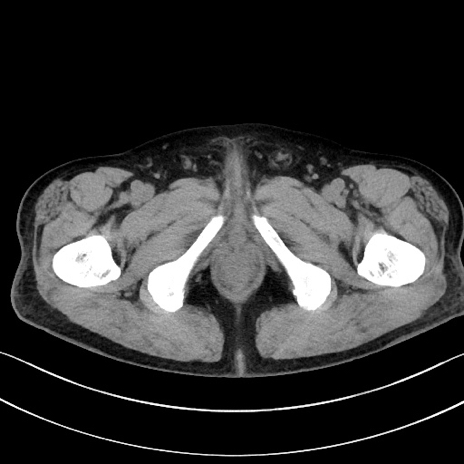

症例15(横断像)

【症例】70歳代男性

【主訴】腹痛

【現病歴】今朝から腹痛あり。全体的に痛い。特に左上の方。排ガスが今日はない。冷や汗が出る。

【既往歴】直腸癌術後

【身体所見】左側腹部〜上腹部に圧痛あり。腹膜刺激症状明らかなではない。軽度反跳痛。左下腹部に術後瘢痕あり。

【データ】WBC 7700、CRP 0.02